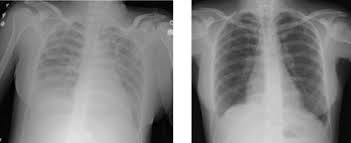

Managing Ards With Noninvasive Ventilation Niv Medmastery

Managing Ards With Noninvasive Ventilation Niv Medmastery from www.medmastery.com

This deprives your organs of the oxygen they need to function. On a microscopic level, the disorder is associated with capillary endothelial injury and diffuse alveolar damage. The fluid prevents your lungs from filling with oxygen. Care guide for ards (acute respiratory distress syndrome) (discharge care). The fluid keeps your lungs from filling with enough air, which means less oxygen reaches your bloodstream. Acute respiratory distress syndrome (ards) is a serious lung condition that causes low blood oxygen. People who develop ards often are very ill with another disease or have major injuries. It occurs when fluid fills up the air sacs in your lungs.

On a microscopic level, the disorder is associated with capillary endothelial injury and diffuse alveolar damage. Most people who get ards are already at the hospital for trauma or illness. The outcomes tend to be better in younger patients, trauma patients and when ards is caused by blood transfusions. Acute respiratory distress syndrome (ards) is a condition that causes fluid to build up in your lungs so oxygen can't get to your organs. The american lung association (ala) says ards is a rapidly progressive disease that can occur in critically ill patients—most notably now, in those diagnosed with severe illness resulting from. Most people who develop ards are in the hospital for other serious health problems. In ards, fluid builds up inside the tiny air sacs of the lungs, and surfactant breaks down. The condition causes fluid to accumulate in the lungs, which in turn reduces blood oxygen to dangerously low levels. The diagnosis of ards is based on fulfilling three criteria: Care guide for ards (acute respiratory distress syndrome) (discharge care). People who develop ards are usually ill due to another disease or a major injury. Possible causes, signs and symptoms, standard treatment options and means of care and support. Ards is a medical emergency.

Ards, or acute respiratory distress syndrome, is a lung condition that leads to low oxygen levels in the blood. Covid‐19 ards is a predictable serious complication of covid‐19 that requires early recognition and comprehensive management this disease is still too strange to us, and there are too many doubts, says dr ling qin (lq), after reviewing more than 400 patients with coronavirus disease 2019 (covid‐19) pneumonia in wuhan union hospital, china. In ards, fluid builds up inside the tiny air sacs of the lungs, and surfactant breaks down. Acute respiratory distress syndrome (ards) is a form of acute lung injury and occurs as a result of a severe pulmonary injury that causes alveolar damage heterogeneously throughout the lung. Most people who get ards are already at the hospital for trauma or illness. Causes may include sepsis, pancreatitis, trauma, pneumonia, and aspiration. Ards is a type of acute respiratory failure caused by fluid buildup in your lungs. Acute respiratory distress syndrome (ards) is a medical condition in which the lungs are not working properly and oxygen blood levels are too low.